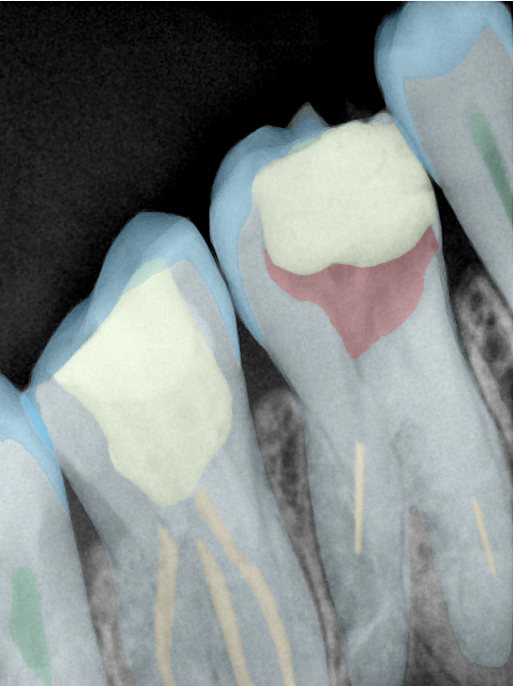

CR/DR 牙齿分割阶段记录

当前进展

- 完成了 CR/DR 牙齿相关分割训练

- 当前结果已经达到阶段预期,但仍有细节问题需要继续处理

相关测试

遇到的问题

- 训练过程中出现过 mask 下移问题

- 部分结果会出现 box 填充异常

- mask 边缘仍然有比较明显的锯齿感

参考

第二版算法问题测试

结论:修复类出现了不鲁棒的情况,后续需要加入轮廓的扩充数据进行增强。